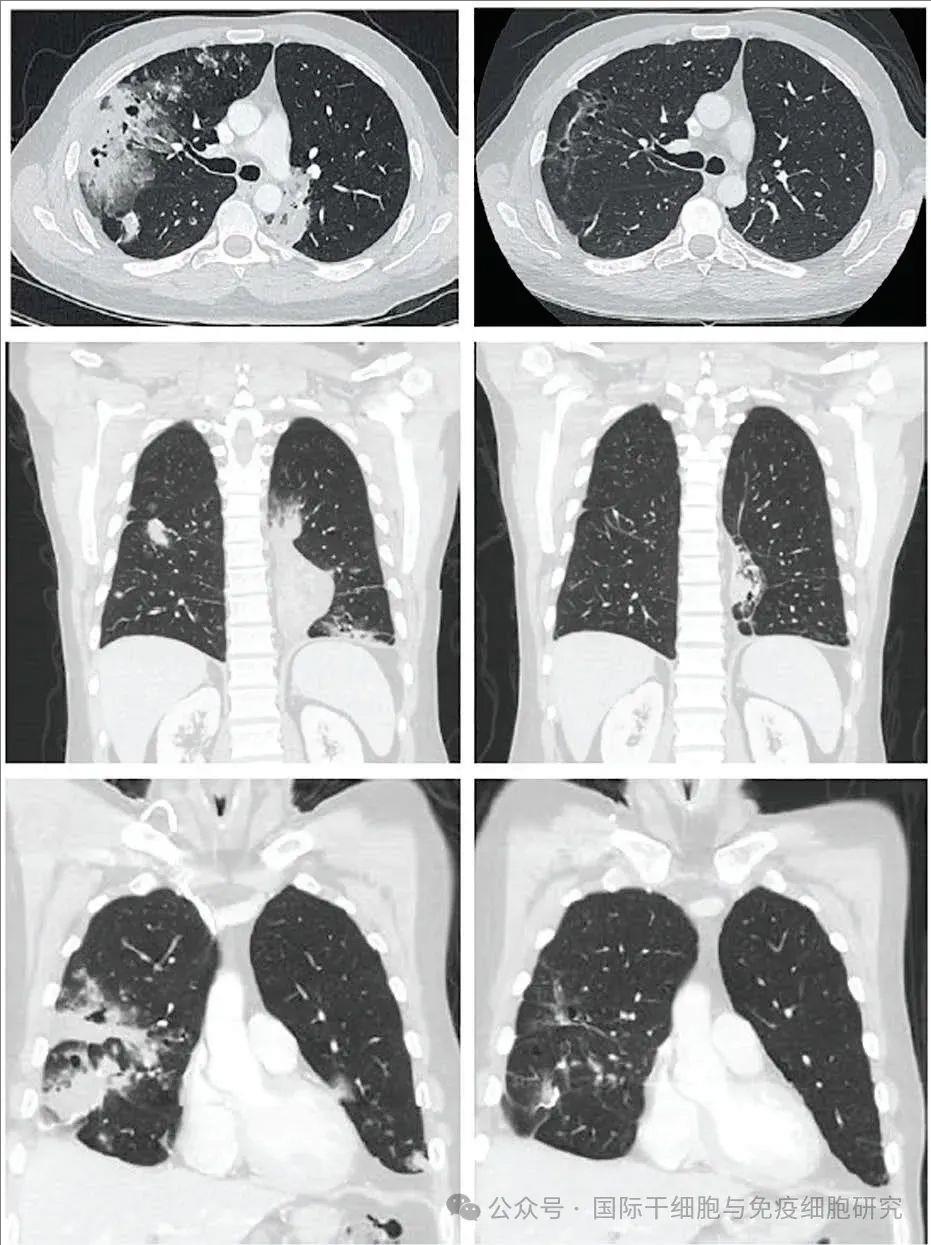

其实,Barker并不是唯一一例经TIL治疗后,病情缓解的非小细胞肺癌患者。《癌症探索(Cancer Discov)》就曾于2024年5月,报道过一位41岁IV期肺黏液腺癌的男性患者,在TIL治疗3个月后,获得部分缓解(PR)的惊艳案例!

这位患者在TIL回输前后复查CT显示,反应持续时间分别为1.1+(TIL治疗前)、26.2+个月(TIL治疗6周后),更为欣喜的是,随着时间推移,反应不断加深。最终在TIL治疗12周(3个月)时,获得81%的部分缓解(PR)(详见下图)。

▲图源“Cancer Discov”,版权归原作者所有,如无意中侵犯了知识产权,请联系我们删除